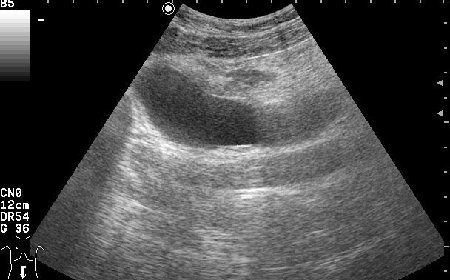

Женщина 42 лет с болями внизу живота, дизурическими явлениями, повышением температуры.

Сонограммы мочевого пузыря

Похоже на опухоль, но по анамнезу я больше склоняюсь к воспалению урахуса!

Согласна с первым постом-возможно нагноение урахуса(и клиника подходит)